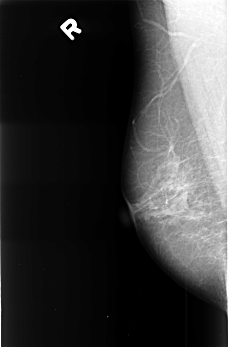

B_3397_1.RIGHT_MLO

RIGHT_MLO LINES 4504 PIXELS_PER_LINE 2976 BITS_PER_PIXEL 12 RESOLUTION 50 NON_OVERLAY